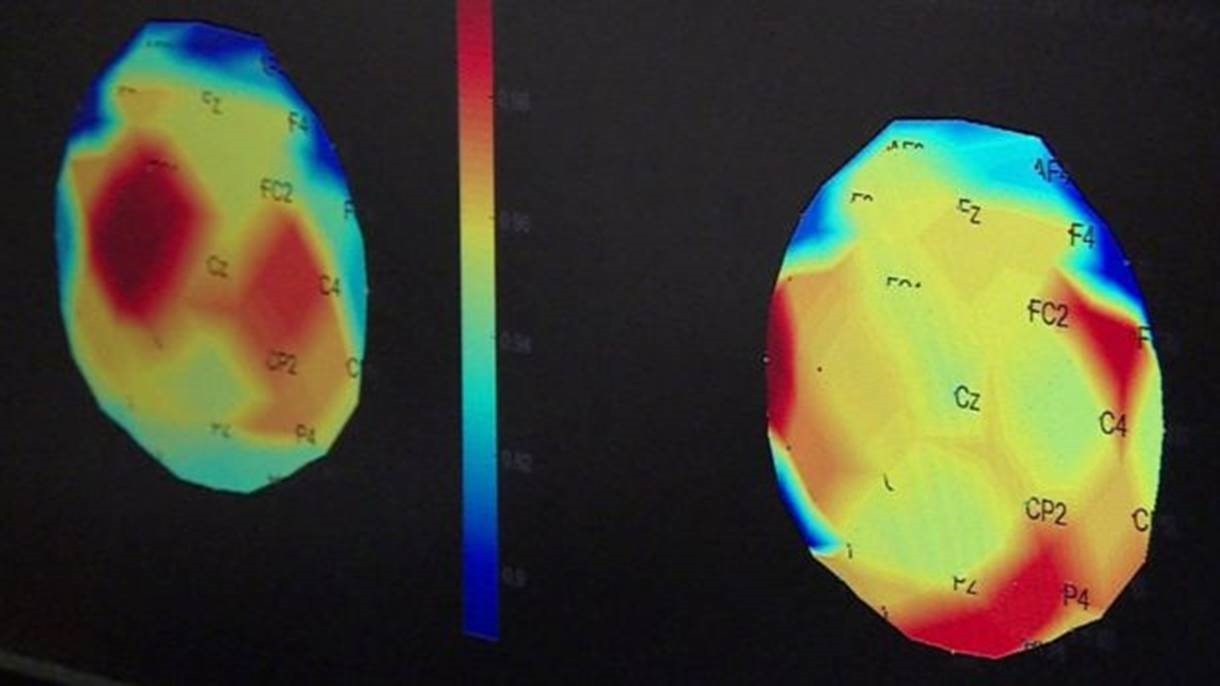

Partes do cérebro responsáveis pelos movimentos (em vermelho na imagem da esquerda) não estavam funcionando adequadamente. Após três meses de tratamento, essas regiões foram reativadas

Tomografias mostram que, antes de os pacientes receberem o tratamento de estimulação elétrica, áreas do cérebro que controlam movimentos não estavam funcionando adequadamente. Alguns meses após o tratamento, essas regiões do cérebro haviam se reativado.